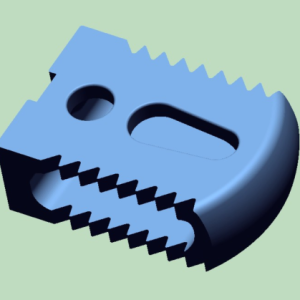

Vật liệu: vật liệu y sinh PEEK

Công nghệ: công nghệ in 3D

Vật liệu: vật liệu y sinh PEEK

Công nghệ: công nghệ in 3D